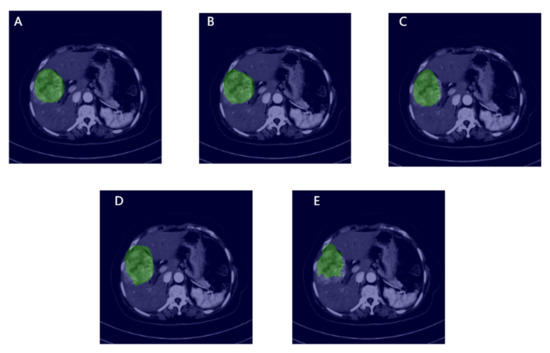

2.3. Manual ROI Annotation

3.4. MVI Prediction Results and Models Comparison